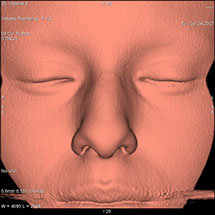

Le scanner comporte un lit d'examen, sur lequel le patient est allongé, qui va se déplacer lentement pendant l’examen et un anneau qui va tourner autour du patient en émettant des rayons X (il contient le tube à rayons X et les récepteurs). Les rayons X vont traverser la région à étudier et permettre d’obtenir des images en coupe de la zone à étudier. Des traitements de numérisation informatique permettront d'obtenir  des images 2D ou 3D dans différents plans et volumes.

• Les pelvimétries.